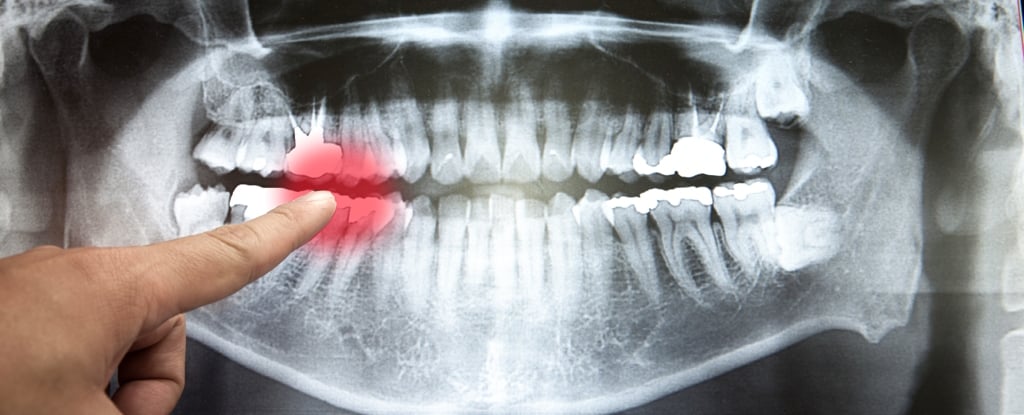

Dentists prescribed over 2.3 million clindamycin prescriptions last year despite a decades‑old black‑box warning for serious C. difficile infections, even as overall dental antibiotic use rose about 6% from 2020 to 2025. The investigation ties unnecessary dental antibiotic prescribing to higher C. difficile risk and antimicrobial resistance, highlighting how private dental practice has lagged in antibiotic stewardship and guideline updates, with the story of Dolores Owens illustrating the potential harms of such prescribing.